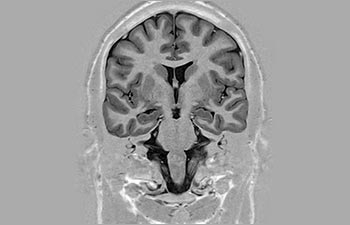

Cerebro

Información general sobre el cerebro